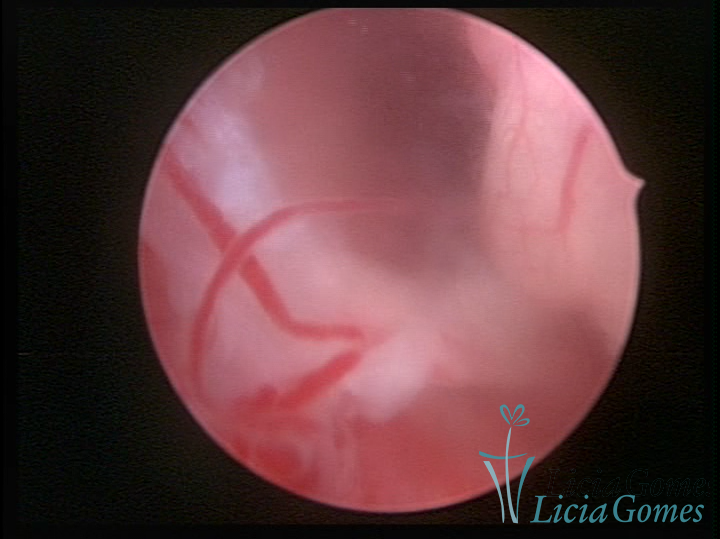

Este pode apresentar uma gama variável de aspectos macroscópicos, com aspecto pseudopolipoide; lembrando tecido cerebroide ou com reação deciduoide;a vascularização superficial é mais evidente e com vasos em formatos de saca-rolha ou espirais visualizando também a vascularização com atípias, com aumento do calibre dos vasos superficiais, pode ser encontrado também tecido em necrose, poderá haver um pequenos dendritos (papilomatoso).